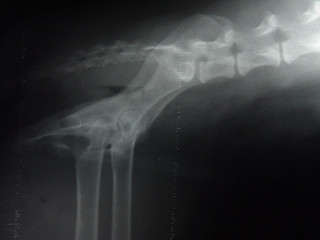

Ninja's Hips (Lateral View)